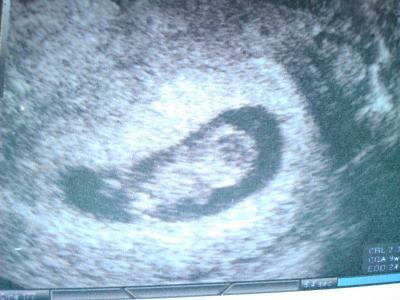

Hallo ihr Lieben nachdem ich nun gestern endlich meinen 2.FA-Termin hatte und ich mehr als nervös war, bin ich nun etwas beruhigter. Den kleinen Gummibärchen geht es gut, das Herzchen schlägt fleissig und bewegt hat es sich auch schon. Gross ist es 2,36 cm und laut US bin ich einen Tag weiter. Dann kam gestern mal wieder das Thema NFM auf und ich habe mich dagegen entschieden. Was der FA auch total verstanden hat. Sie will einen da nichts einreden und sie weiss, das sich für mich nichts ändern würde, wenn die Messung auffällig wäre. Meinen nächsten Termin hab ich leider erst am 16.03 und da wird dann das 1.Screening gemacht. Jetzt werde ich mal versuchen das Bild mit anzuhängen. Nachdem ich gestern abend mein Handy dabei gekillt habe. Liebe Grüsse Nadine

Bild zu Bericht von gestern - Forum für September - Mamis

Oh, so ein schönes Bild vom Bauchwurm!!!

Das sieht doch richtig toll aus. Ach ich könnte die ganze Zeit Gummibärenbilder anschauen Freue mich sehr für Dich. LG Dani